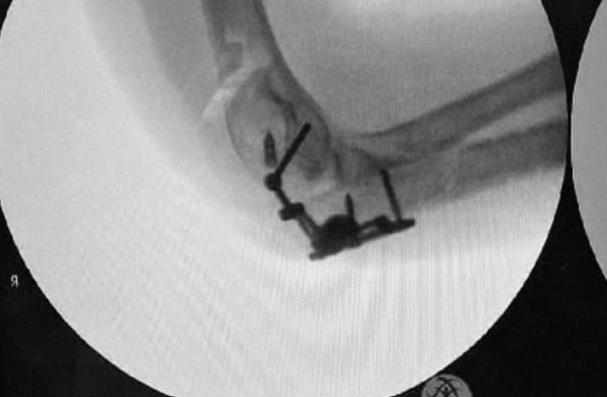

Minimally invasive arthroscopic procedures

Surgical fixation of fractures